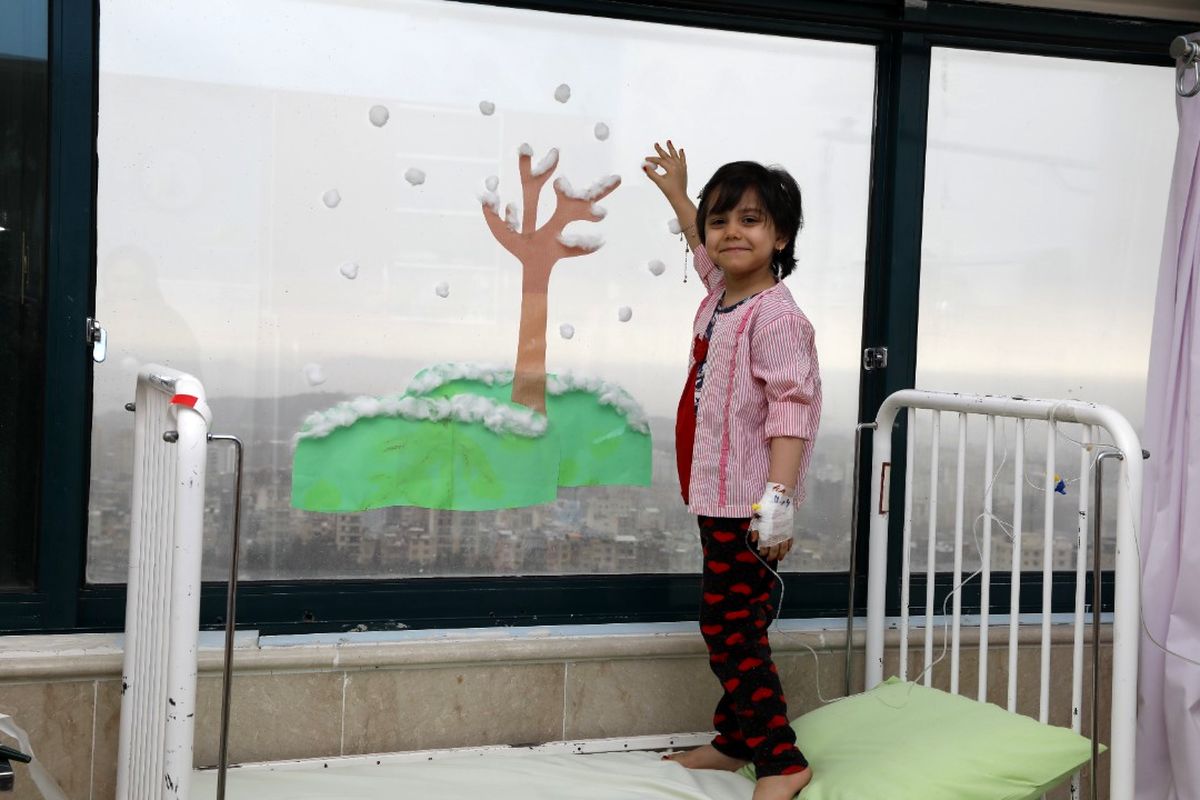

فراخوان کمک برای کودک هموطن مبتلا به سرطان

به گزارش برنا، این کودک سرطان دارد و هزینه هربار تهیه آمپول و داروهایش، به هفت میلیون تومان می رسد که هماکنون به ۶۰ میلیون تومان نیاز دارد.

همچنین مادر به دلیل بیماری داخلی، شرایط بد و اسف باری دارد و به مبلغی نزدیک به ۱۰میلیون نیاز است به همین دلیل موسسه خیریه مبشران نور لا کمک خیران و مردم در حال جمعآوری کمک است تا بتواند به این خانواده سلامتی و امید هدیه دهد.